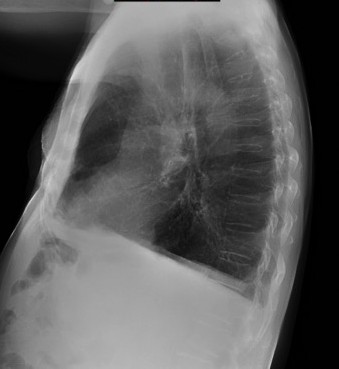

Nota: ¡¡¡No olvidar la placa lateral!!! La regla a seguir es la misma. Leer abdomen y diafragma, examinar parte posterior, tejidos blandos y subir por la columna; tráquea y descender por mediastino. Finalmente pulmones.

Solución: Es un estudio Normal. Silueta cardiomediastínica y parénquimas pulmonares sin alteraciones significativas.